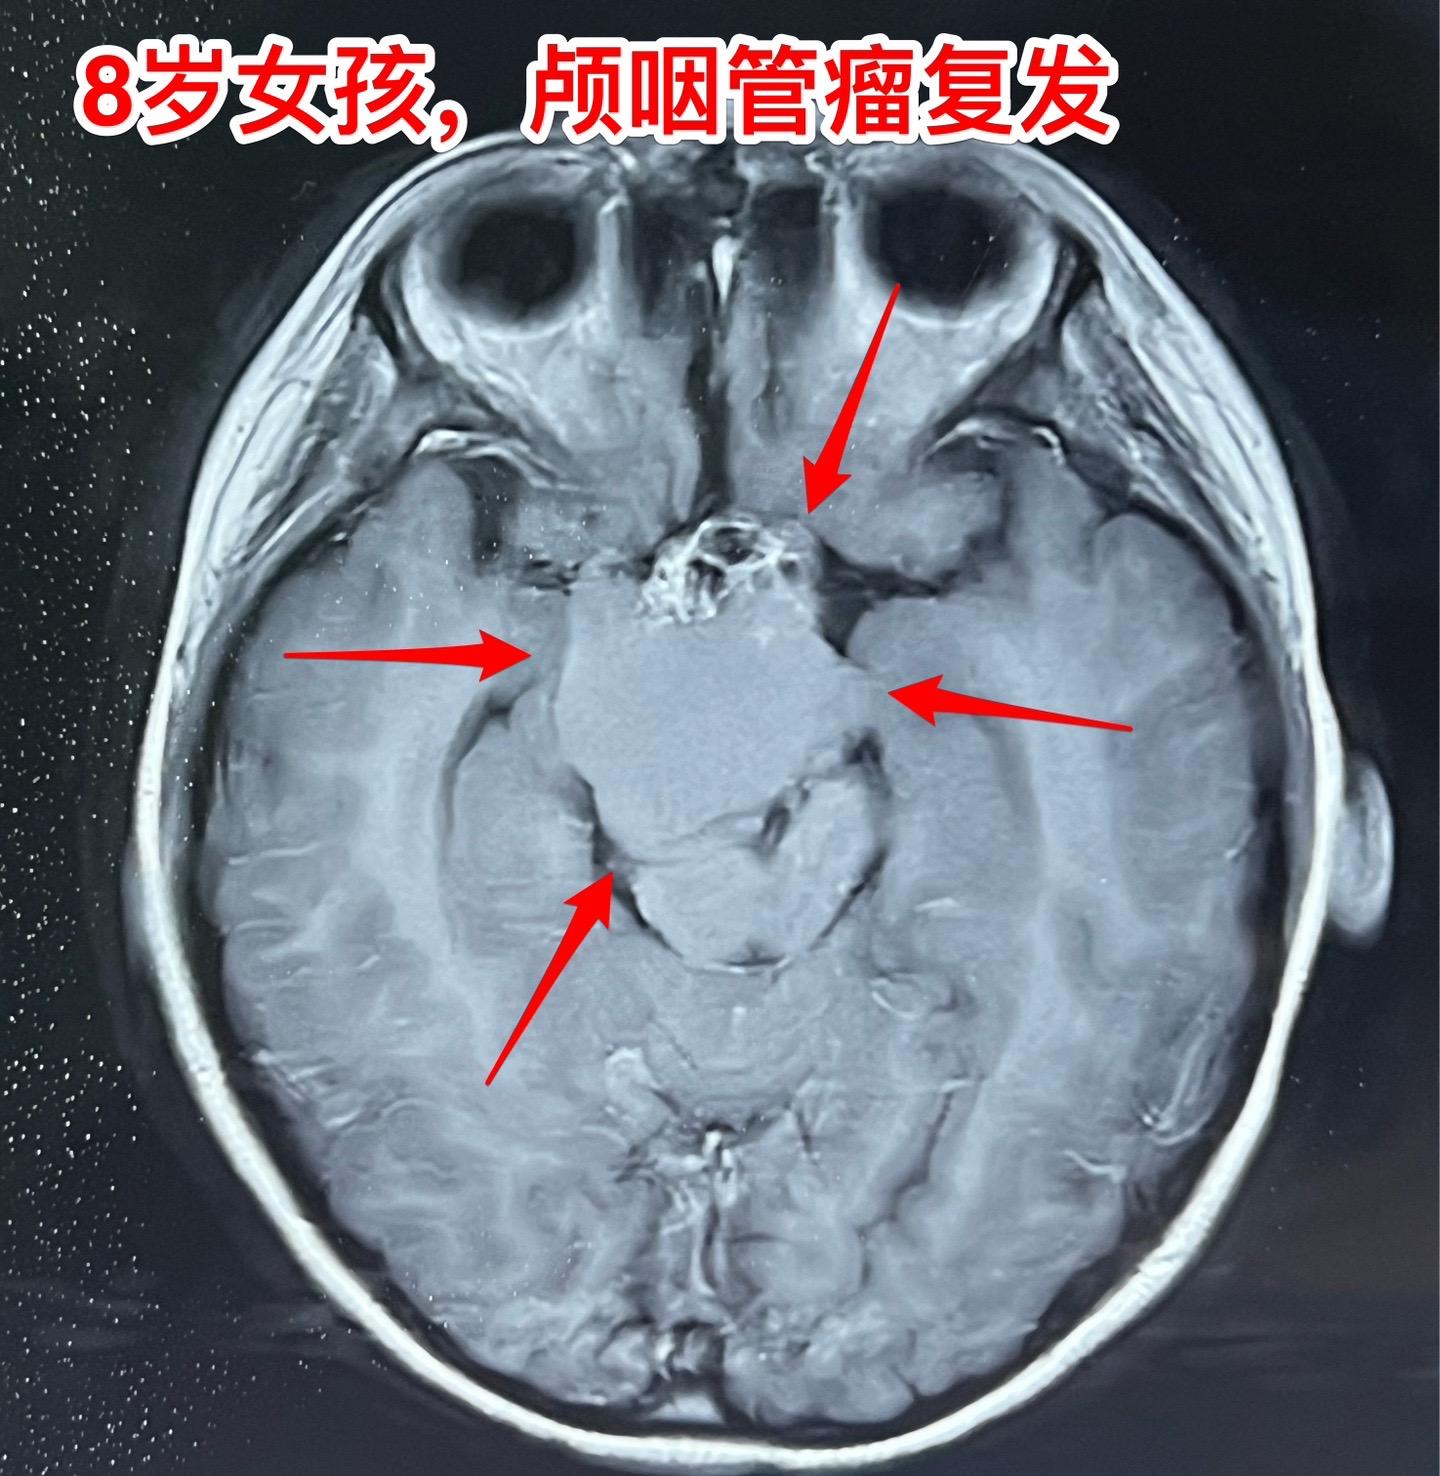

八岁女孩,终于完成了颅咽管瘤切除手术。8岁承德市围场县女孩子,颅咽管瘤手术后两年复发了,视眼视力很差。10月份曾经在我科住院,准备做手术。我在10月31日发的视频中跳舞的就是这个女孩子。当时因为经济原因和医保方面的障碍,未能作手术,回家筹集资金。 12月11日小女孩再次来住院。经过四十多天的等待,小女孩的病情更加恶化了,她的双眼视力更差了,几乎看不见了。磁共振和CT可以显示肿瘤体积巨大。 12月13日作了开颅手术,手术过程顺利。手术后小女孩很快就清醒了,昨晚就转回了普通病